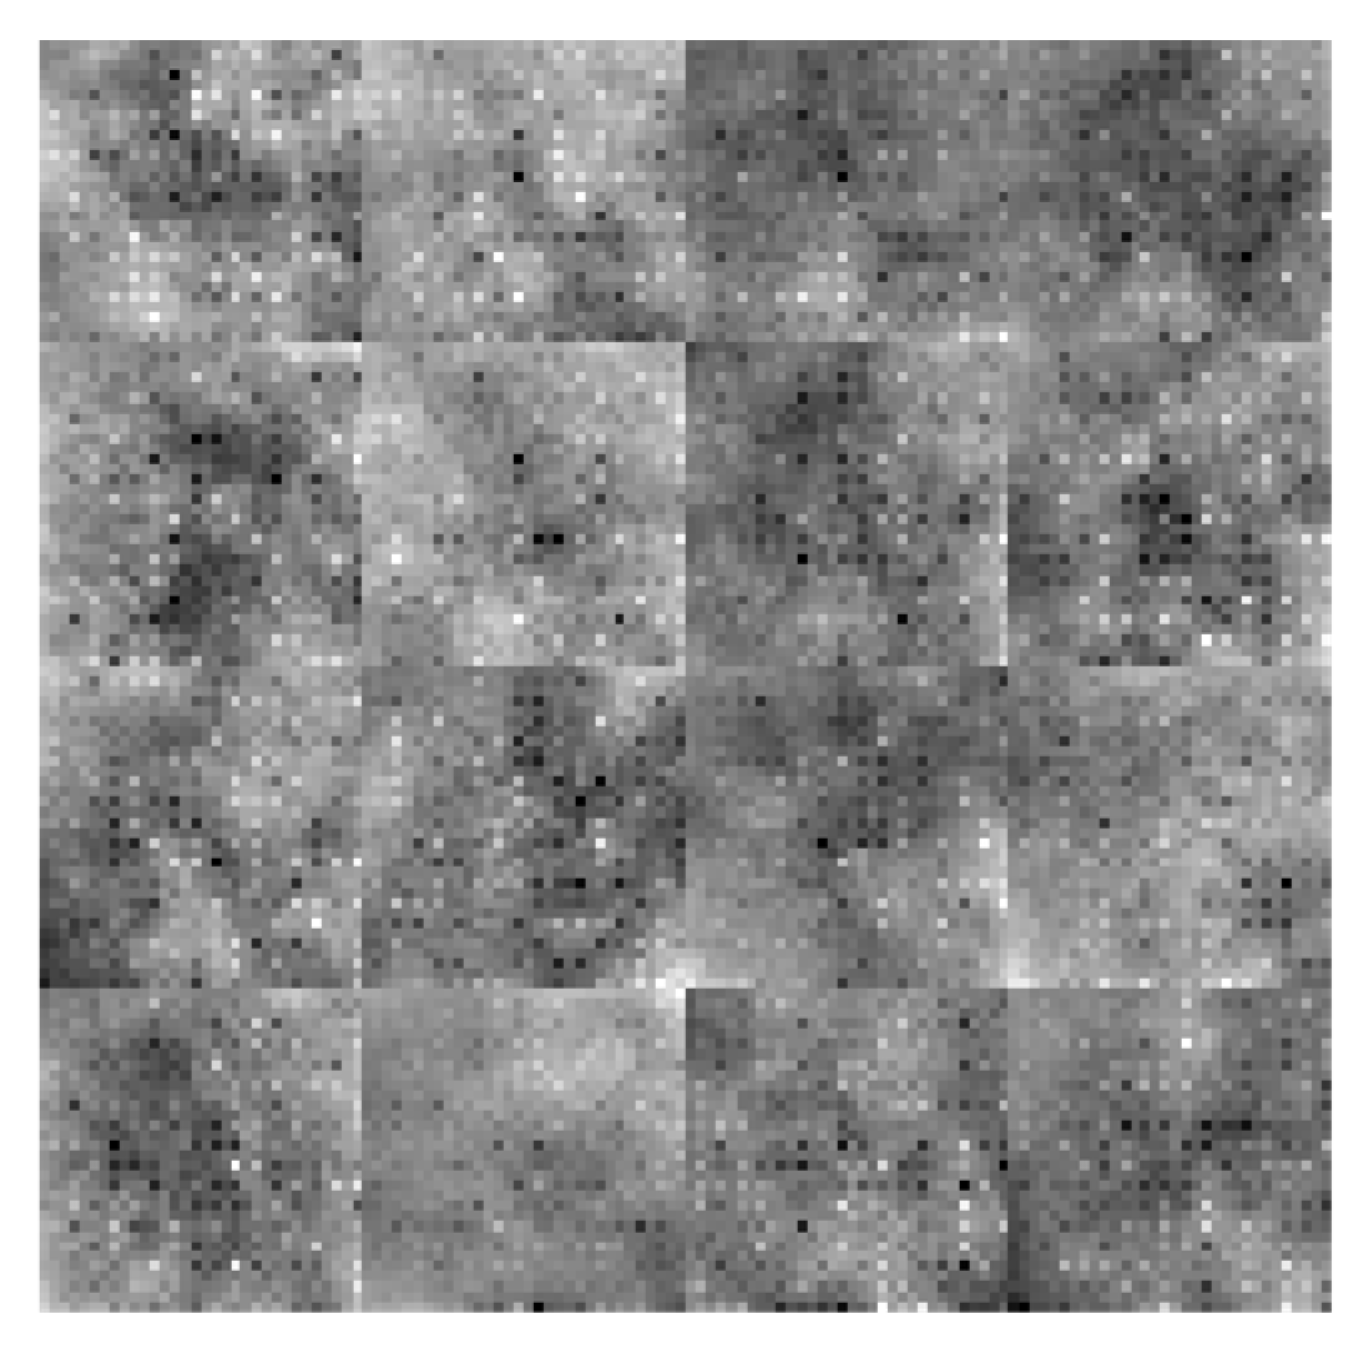

3.4.4. Feature Map of Dilated Convolutional Layers

A CNN feature map represents specific attributes in the input image as the result of a convolutional layer. It is produced by filtering input images or the previous layers' feature map output. The feature maps that are acquired from every convolutional layer are presented in

Figure 5 and

Figure 6. In

Figure 5, the low-level and coarse features of the three convolutional layers conv_1, conv_3, and conv_4 having filters of 128, 96, and 96 are displayed. The feature maps in this figure are primarily composed of coarse and local features which represent the texture in an image. In this local path, a dilated CNN algorithm that has DFs associated with (

= 4,

= 2,

= 1) is referred to as dilated PDCNN (4, 2, 1). In Figure6, the high-level feature maps include contour representations, shape descriptors and fine features of the deeper three convolutional layers conv_2, conv_5, and conv_6 having the same filters, are shown. DFs corresponding to (

=2,

= 1,

= 1) are used in this global path. The multiscale feature maps, which are displayed in

Figure 7, are greatly improved when these features are combined using a feature fusion technique.

Figure 8 displays the final multiscale features that are extracted, along with a fully connected layer that is prevented from overfitting by employing the dropout technique.

Local & Coarse Features (conv_1[DF:4*4], conv_3[DF:2*2], and conv_4[DF:1*1])

Figure 5.

Local and Coarse feature maps of various convolutional layers of the Dilated PDCNN (a) Feature map of conv_1-layer (b) Feature map of conv_3-layer (c) Feature map of conv_4-layer.

Global & Finer Features (conv_2[DF:2*2], conv_5[DF:1*1], and conv_6[DF:1*1])

Figure 6.

Global and finer feature maps of various convolutional layers of the Dilated PDCNN (a) Feature map of conv_2-layer (b) Feature map of conv_5-layer (c) Feature map of conv_6-layer.